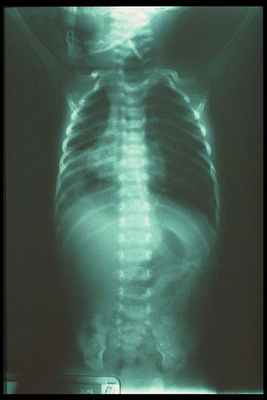

Рентгенография

Рентгенологическая картина зависит от типа атрезии. При отсутствии фистулы с дистальной частью пищевода газ в брюшной полости отсутствует. При наличии дистальной фистулы возникает патологический метеоризм. Дистальный карман пищевода может быть визуализирован при наличии рефлюкса из желудка. Дополнительными находками при рентгенографии могуть быть ателектаз, консолидации (пневмония) при аспирации, а также сопутствующие мальформации позвоночника и конечностей.

Далее обязательно проводится рентгенологическое обследование для подтверждения диагноза. На обзорном снимке грудной и брюшной полостей начало зонда определяется в слепом конце пищевода, далее наличие газа в желудочно-кишечном тракте позволяет дифференцировать свищевые формы атрезии пищевода. Отсутствие газа в желудке при обзорной рентгенографии чаще всего связано с отсутствием сочетания атрезии пищевода со свищем в трахею.

На обследовании выполняются рентгеновские снимки грудной клетки и брюшной полости, предварительно в пищевод устанавливают рентген-контрастный зонд. Исследование проводится в прямой проекции в вертикальном положении ребёнка. Оценивают уровень стояния зонда (свёрнутый зонд в слепом верхнем сегменте); газонаполнение желудка и кишечника (при наличии трахео-пищеводного свища между нижним сегментом и трахеей будет определяться воздух в брюшной полости, при отсутствии воздуха в желудке и кишечнике исключается наличие нижнего трахеопищеводного свища).

Во время проведения рентгенологического обследования можно выявить сопутствующие патологии — непроходимость кишечника, пороки развития позвоночника и пневмонию.